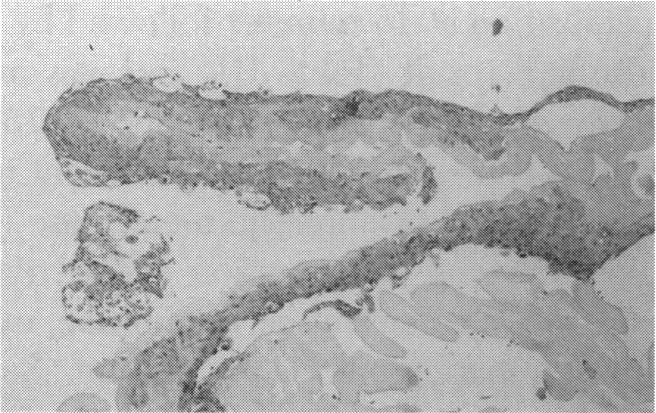

Human Subjects. Of the 19 human subjects included, 18 (20 procedures) underwent in vitro cultured corneal epithelial cell transplants using various carriers for the epithelial cells to determine the most efficacious approach. Sixteen patients (18 procedures on 17 eyes) received autologous transplants, and 2 patients (1 procedure each) received allogeneic sibling grafts. The presumed corneal epithelial stem cells from 1 patient did not grow in vitro. The carriers for the expanded corneal epithelial cells included corneal stroma, type 1 collagen (Vitrogen), soft contact lenses, collagen shields, and amniotic membrane for the autologous grafts and only amniotic membrane for the allogeneic sibling grafts. Histologic confirmation was reviewed on selected donor grafts. Amniotic membrane as carrier. Further studies were made to determine whether amniotic membrane might be the best carrier for the expanding corneal epithelial cells. Seventeen different combinations of tryspinization, sonication, scraping, and washing were studied to find the simplest, most effective method for removing the amniotic epithelium while still preserving the histologic appearance of the basement membrane of the amnion. Presumed corneal epithelial stem cells were harvested and expanded in vitro and applied to the amniotic membrane to create a composite graft. Thus, the composite graft consisted of the amniotic membrane from which the original epithelium had been removed without significant histologic damage to the basement membrane, and the expanded corneal epithelial stem cells, which had been applied to and had successfully adhered to the denuded amniotic membrane. Animal model. Twelve rabbits had the ocular surface of 1 eye damaged in a standard manner with direct removal of the presumed limbal stem cells, corneal epithelium, and related epithelium, followed by the application of n-heptanol for 60 seconds. After 6 weeks, all damaged eyes were epithelialized and vascularized. Two such treated eyes were harvested without further treatment, to be used for histologic study as damaged controls. The remaining 10 rabbits received composite grafts (consisting of amniotic membrane with expanded allogeneic rabbit corneal epithelial cell transplants) applied to the ocular surface in a standard manner followed by the application of a contact lens. At 16 days following transplantation, 5 of the rabbits were sacrificed and the corneal rims were removed for histologic study. At 28 days, the remaining rabbits were sacrificed and the previously damaged eyes were harvested for histologic and immunohistochemical study.

RESULTS

Human subjects. Of the 19 total patients admitted to the study, the presumed corneal epithelial stem cells of 1 patient did not grow in vitro. Of the remaining 18 patients (20 procedures, 19 eyes), 3 patients had unsuccessful results (3 autologous procedures), 1 patient had a partially successful procedure (allogeneic procedure), and 1 patient had a procedure with an undetermined result at present (allogeneic procedure). One unsuccessful patient had entropion/trichiasis and mechanically removed the graft and eventually went into phthisis. The other 2 unsuccessful patients suffered presumed loss of autologous donor epithelium and recurrence of the ocular surface disease (pterygium). The partially successful patient receiving an allogeneic transplant had infectious keratitis delay of his re-epithelialization; he has only minimal visual improvement but has re-epithelialized. The patient receiving the second allogeneic graft lost his donor epithelium at day 4. Additional donor epithelium was reapplied, but the result is undetermined at present. Amniotic membrane as carrier. The in vitro preparation of the amniotic membrane with corneal epithelial stem cell graft overlay was successful. Histology documented removal of the amniotic epithelium and reapplication of corneal epithelial cells. Animal model. The 2 rabbits that had no reparative surgery following standard ocular surface injury had histology and immunopathology consistent with incomplete corneal epithelial stem cell failure with vascularization and scarring of the ocular surface. Light microscopy and immunohistologic staining with AE5 confirmed the conjunctival phenotype of the ocular surface repair but also documented the incomplete model. The allogeneic stern cell transplants had varying results. One rabbit had a suppurative infection and lost the graft. Reparative surgery failed in 2 of the rabbits, failed partially in 3 of the rabbits, was partially successful in 3 others, and was successful in 1 rabbit at 28 days. Histologic and immunopathologic study documented successful growth of corneal epithelium onto the recipient surface.

人类受试者。纳入的19名人类受试者中,18名(20例手术)使用上皮细胞的各种载体进行了体外培养角膜上皮细胞移植,以确定最有效的方法。16例患者(17只眼的18例手术)接受了自体移植,2例患者(各1例手术)接受了异体同胞移植。1例患者的假定角膜上皮干细胞在体外未生长。扩增角膜上皮细胞的载体包括角膜基质、1型胶原蛋白(Vitrogen)、软性隐形眼镜、胶原盾和羊膜用于自体移植,而异体同胞移植仅使用羊膜。对选定的供体移植物进行了组织学确认。羊膜作为载体。进一步研究以确定羊膜是否可能是扩增角膜上皮细胞的最佳载体。研究了17种不同的胰蛋白酶消化、超声处理、刮除和冲洗组合,以找到去除羊膜上皮同时仍保留羊膜基底膜组织学外观的最简单、最有效的方法。采集假定的角膜上皮干细胞并在体外扩增,然后应用于羊膜以制备复合移植物。因此,复合移植物由已去除原始上皮且基底膜无明显组织学损伤的羊膜以及已应用并成功粘附于裸露羊膜的扩增角膜上皮干细胞组成。动物模型。12只兔子的1只眼的眼表以标准方式受损,直接去除假定的角膜缘干细胞、角膜上皮和相关上皮,然后应用正庚醇60秒。6周后,所有受损眼均上皮化且血管化。2只经如此处理的眼未进一步治疗即被采集,用作组织学研究的受损对照。其余10只兔子接受以标准方式应用于眼表的复合移植物(由带有扩增异体兔角膜上皮细胞移植的羊膜组成),随后应用隐形眼镜。移植后16天,处死5只兔子,取出角膜缘进行组织学研究。28天时,处死其余兔子,取出先前受损的眼进行组织学和免疫组织化学研究。

结果

人类受试者。纳入研究的19例患者中,1例患者的假定角膜上皮干细胞在体外未生长。其余18例患者(20例手术,19只眼)中,3例患者手术结果不佳(3例自体手术),1例患者手术部分成功(异体手术),1例患者目前手术结果未确定(异体手术)。1例手术失败的患者患有睑内翻/倒睫,机械性移除了移植物,最终眼球萎缩。另外2例手术失败的患者假定自体供体上皮丢失且眼表疾病(翼状胬肉)复发。接受异体移植的部分成功患者发生感染性角膜炎,上皮化延迟;他的视力仅略有改善,但已重新上皮化。接受第二次异体移植的患者在第4天失去了供体上皮。重新应用了额外的供体上皮,但目前结果未确定。羊膜作为载体。羊膜与角膜上皮干细胞移植物覆盖物的体外制备成功。组织学证实羊膜上皮已去除且角膜上皮细胞已重新应用。动物模型。2只在标准眼表损伤后未进行修复手术的兔子的组织学和免疫病理学结果与角膜上皮干细胞不完全衰竭一致,伴有眼表血管化和瘢痕形成。光学显微镜检查和用AE5进行的免疫组织化学染色证实了眼表修复的结膜表型,但也记录了不完全模型。异体干细胞移植结果各异。1只兔子发生化脓性感染,移植物丢失。2只兔子的修复手术失败,3只兔子部分失败,另外3只部分成功,1只兔子在28天时成功。组织学和免疫病理学研究记录了角膜上皮在受体表面的成功生长。